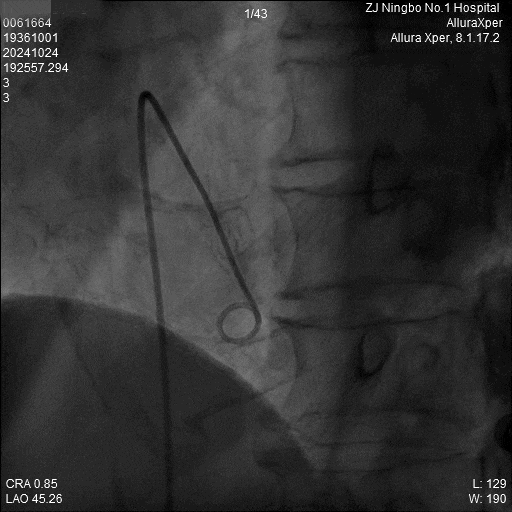

4.旋入起搏器:回撤保护套筒至下腔,释放调弯,调整张力开始旋入旋入0.5圈及1.0圈分别测试参数,等待扭矩传递。

5.旋入后立即进入对接栓模式,并调弯测试。